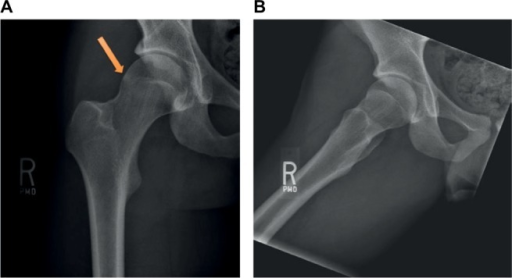

Describe the imaging findings in FAI. What measurements define cam and pincer morphology?